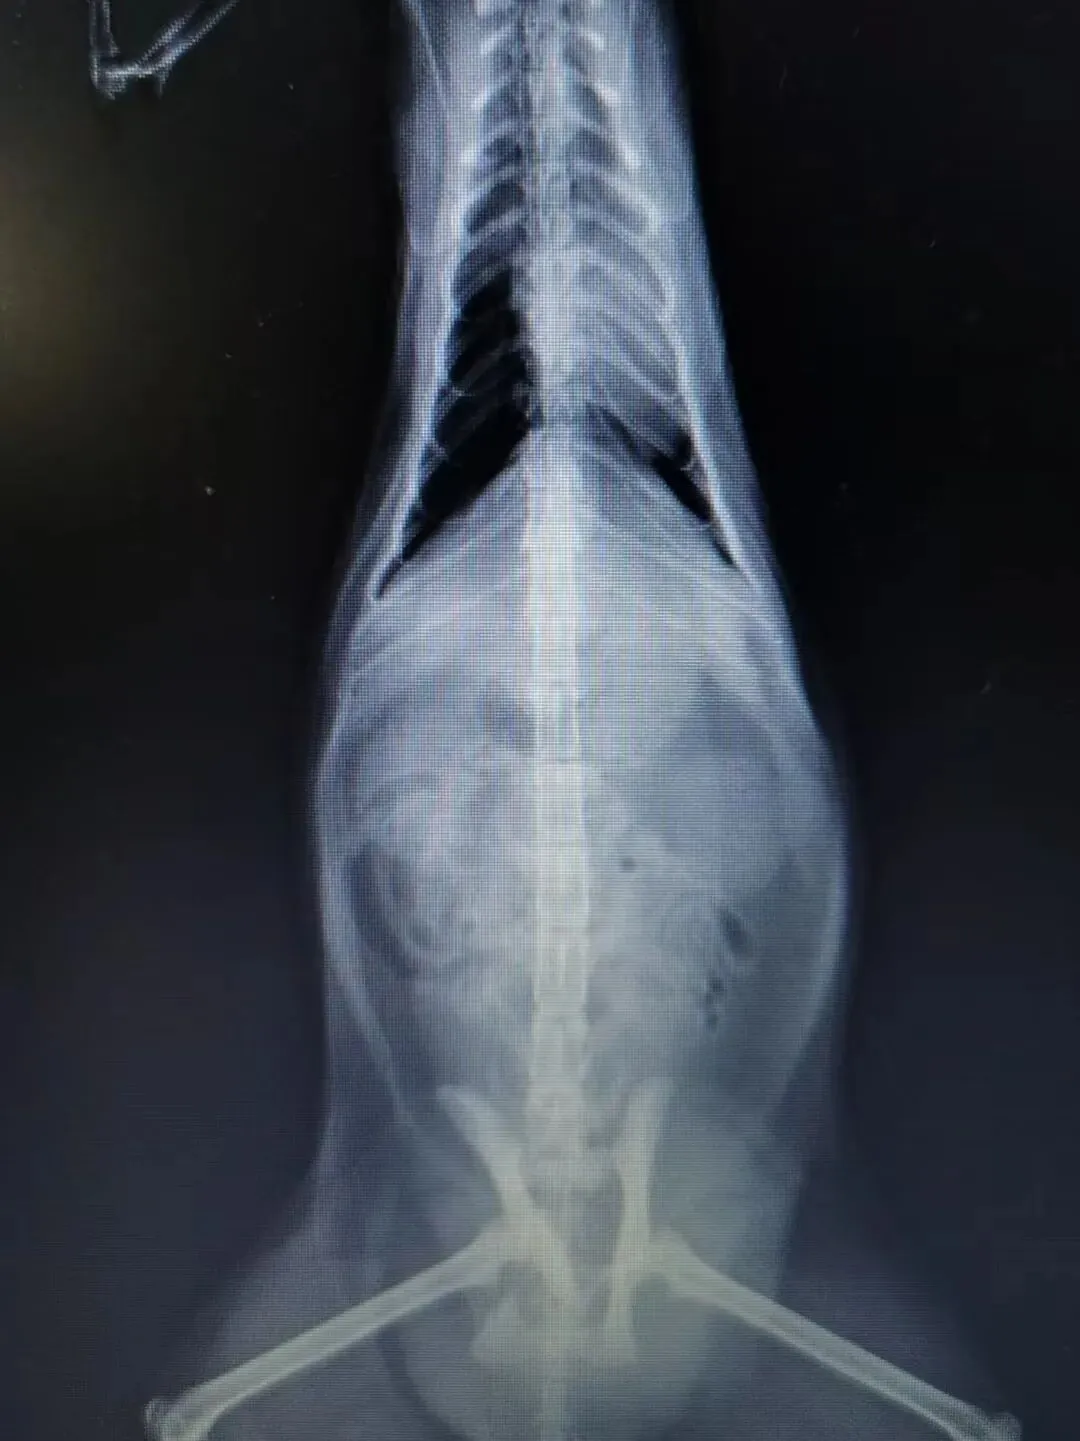

就医检查:鸡腿后肢在医生被触摸时仍有痛觉反应,经判断大概率为盆骨骨折,且右后脚带有明显伤口,具体情况需拍摄X光片来确定。鸡腿连袋重:4.95kg。

盆骨X光片:盆骨粉碎性骨折,因十号的生化血常规和SAA指标达标,于是准备12号进行手术。